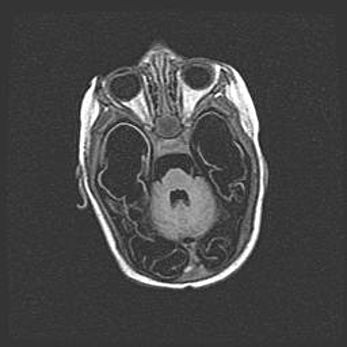

Мальформация Денди-Уокера. Киста задней черепной ямки.

Агенезия мозолистого тела.

Возраст: 2,5 месяца

Вес: 2420 г

Пол: женский

Окружность головы: 37 см

Срок гестации: 32 недели

Мальформация Денди—Уокера — редкий вид патологии ЦНС, представляющий собой врожденный порок развития каудального отдела ствола и червя мозжечка, ведущий к неполному раскрытию срединной (Мажанди) и латеральных (Лушка) апертур IV желудочка мозга. Для этогно синдрома характерна триада симптомов: гипотрофия червя мозжечка и/или полушарий мозжечка, кисты задней черепной ямки, гидроцефалия различной степени. В 70% случаев порок сочетается и с другими аномалиями головного мозга, в частности с агенезией мозолистого тела.